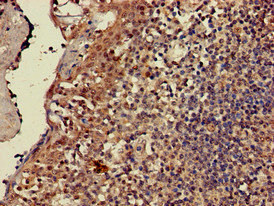

Immunohistochemistry of paraffin-embedded human lymph node tissue using CSB-PA10499A0Rb at dilution of 1:100

Immunohistochemistry of paraffin-embedded human tonsil tissue using CSB-PA10499A0Rb at dilution of 1:100